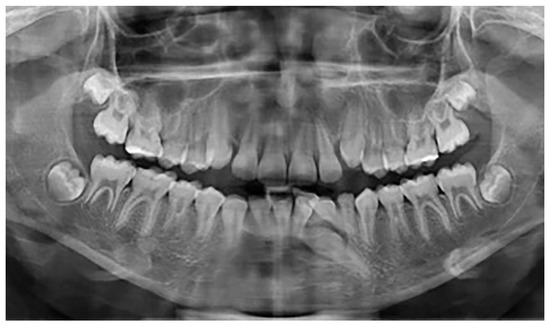

In group B, a total of 13 patients were found to have mandibular canine impaction. Impaction of the canines was bilateral in 1 patient and unilateral in 12 patients, for a total of 14 impacted permanent mandibular canine teeth. Four patients still had retained deciduous canines at the time of diagnosis (Figure 4). In two cases, the impacted canines were transposed in the region of the lateral incisors. Besides these 13 patients with impacted mandibular canines, one (female) of the 640 participants was found to have mandibular canine transmigration. The transmigration was unilateral. In this patient, the primary canine was retained. None of the patients had traumatic episodes, and none of them had systemic disorders. All the patients were asymptomatic.

Figure 4.

Patient with impaction of mandibular canines and retained deciduous canines.